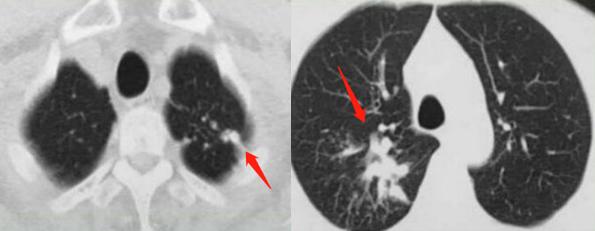

59岁男性,间断咳嗽,咳痰两年:

CT发现双上肺多发病灶,考虑肺结核,建议做个增强扫描排除肿瘤,支气管镜检查也有必要。

结果,同时查到结核杆菌和鳞癌细胞。

这是一位肺结核患者,同时合并肺鳞癌。